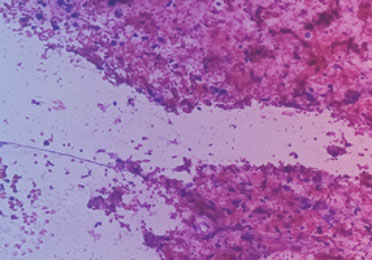

Besteht Verdacht auf eine Krebserkrankung, so wird mittels bildgebender Diagnostik wie Ultraschall, Computertomographie (CT) oder Magnetresonanztomographie (MRT) nach dem möglichen Tumor gesucht.

Um eine bösartige Erkrankung zu bestätigen, ist die Untersuchung einer Tumorgewebeprobe entscheidend.